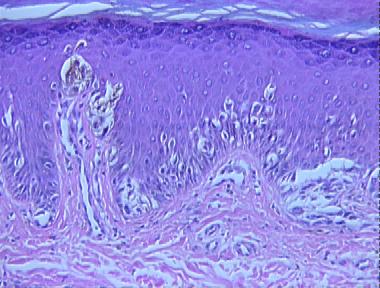

junctional Spitz nevus

Histologic Features

- Hyperkeratosis, hypergranulosis and slight epidermal hyperplasia

- A proliferation of large epthelioid and spindle melanocytes, as single units and nests at the dermoepidermal junction

- Large, uniform melanocytes with abundant eosinophilic cytoplasm

- Single cell proliferation predominate over nests at some foci

- Scatter of melanocytes above the dermo-epidermal junction

- Dull pink globules associated with the nests (Kamino bodies)

- As a whole, the lesion is small (less than 6 mm.), well-circumscribed and symmetrical.